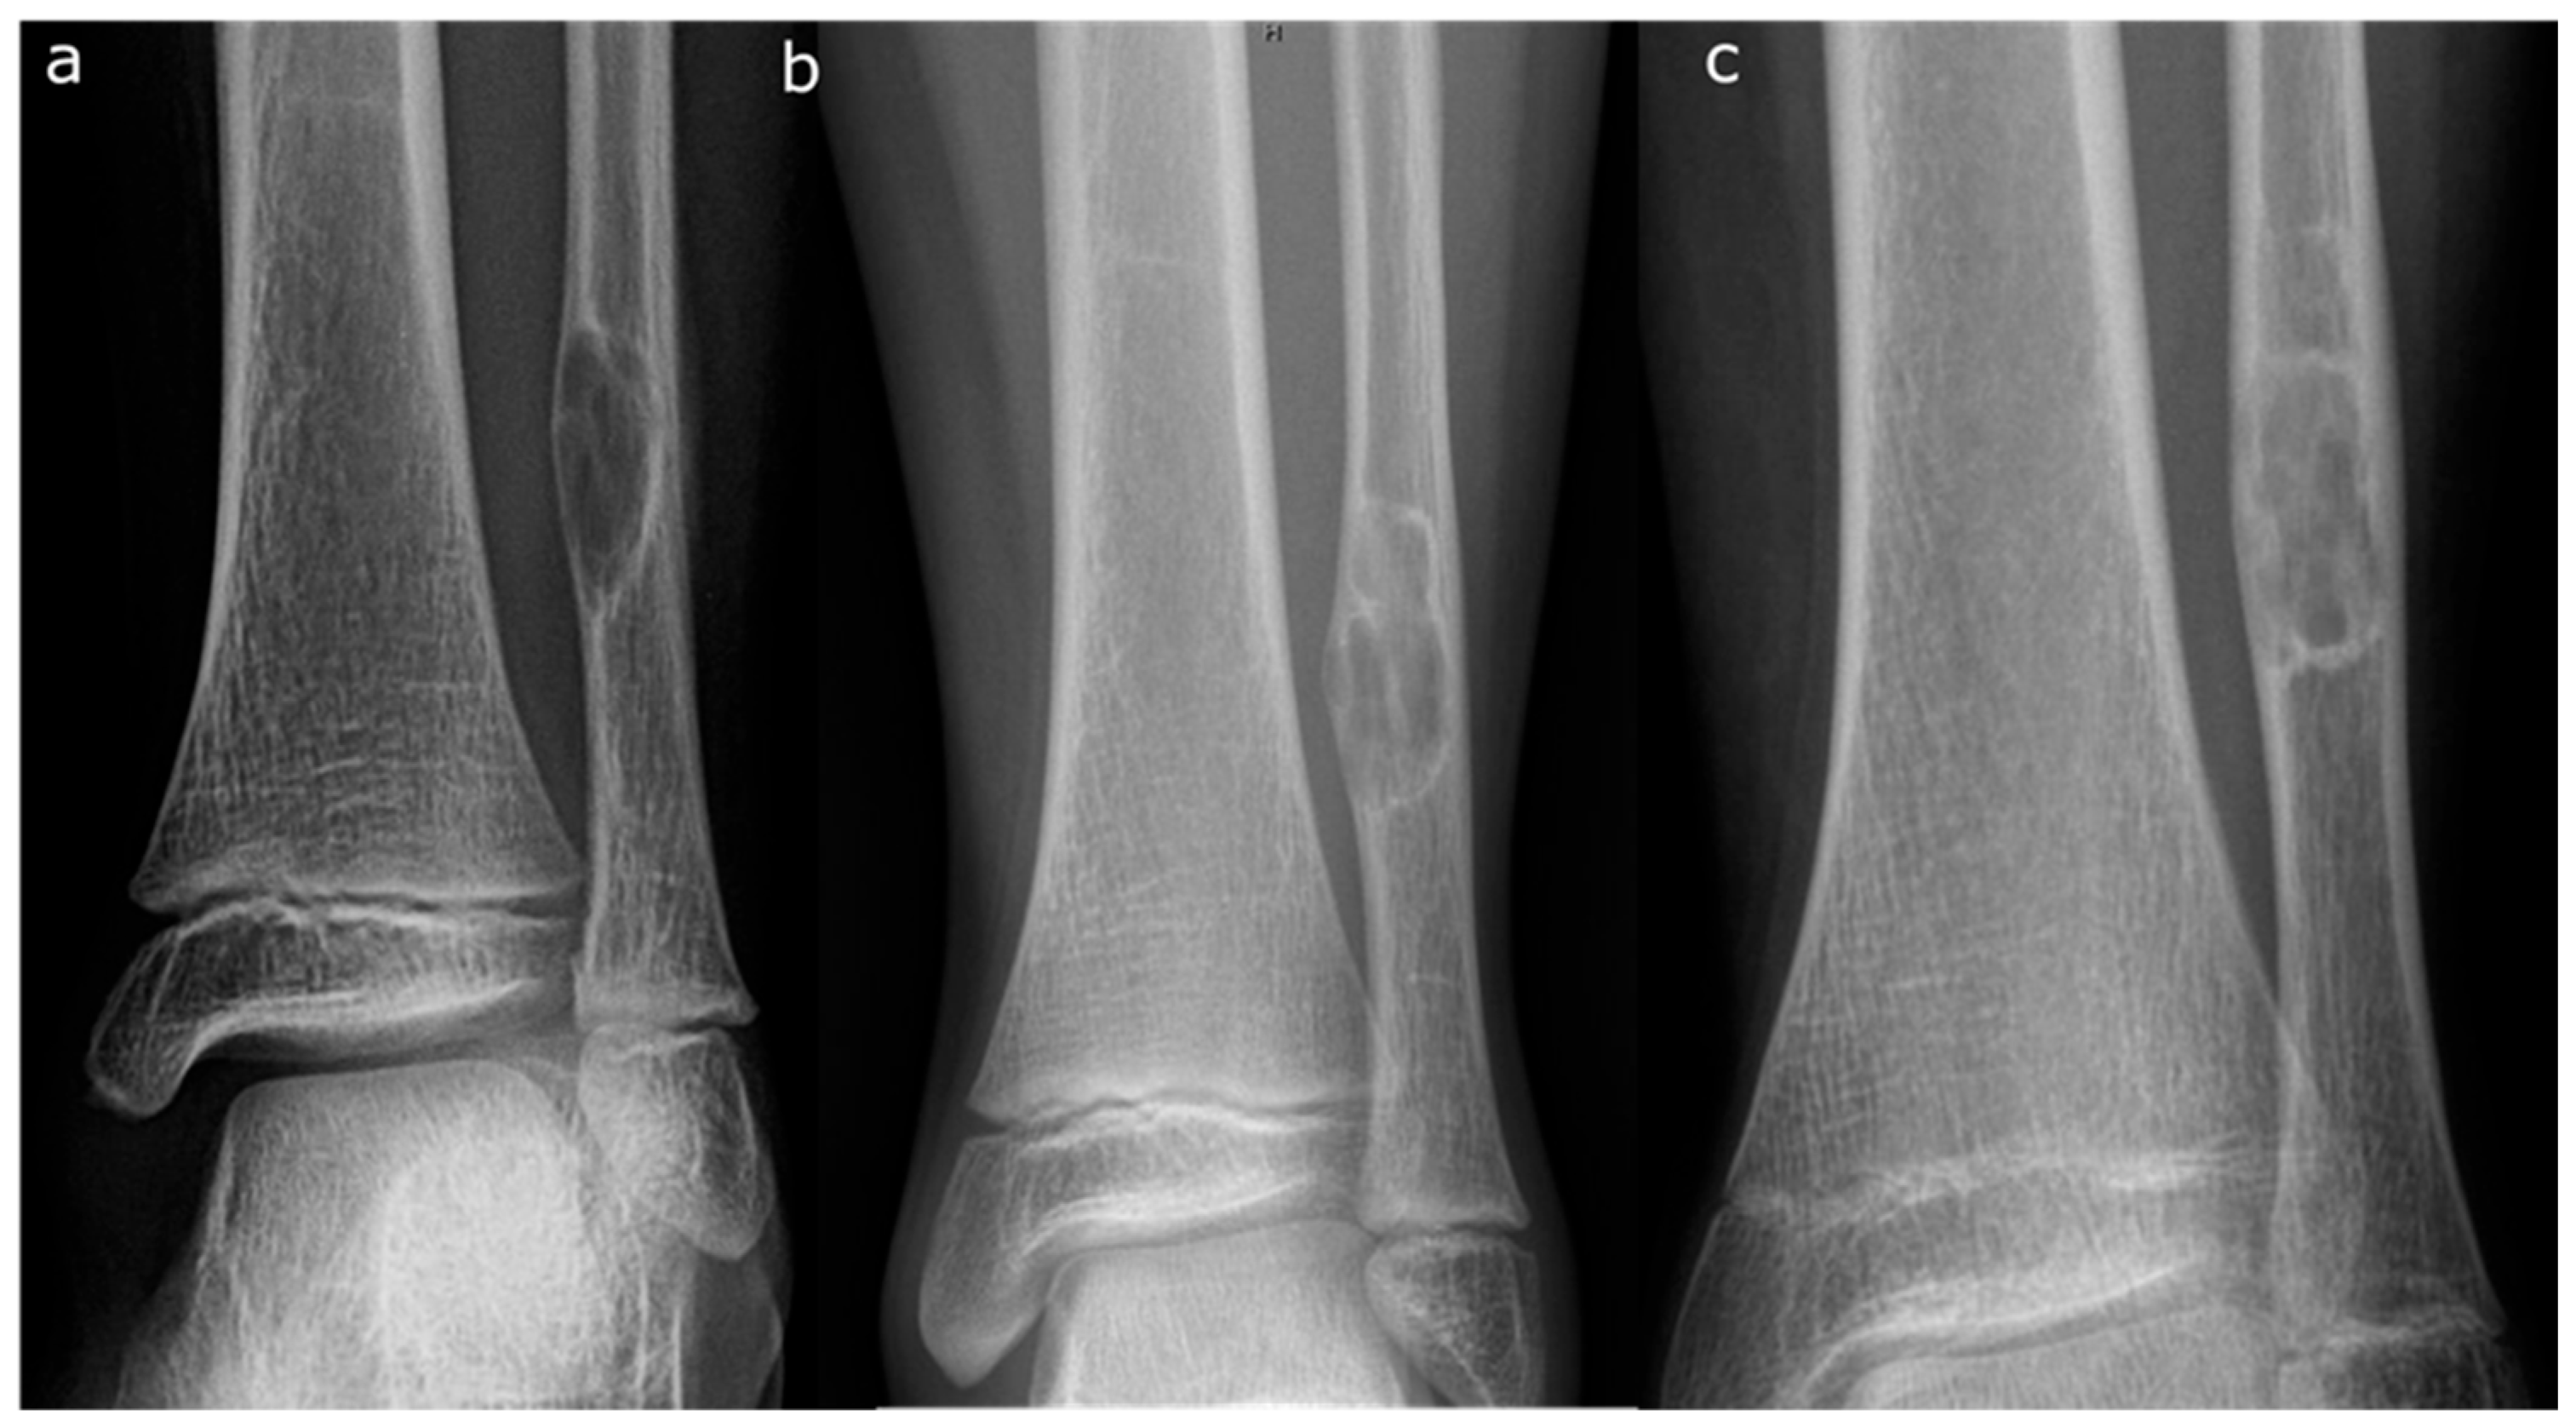

• Curettage and Bone Grafting: This is by far the most performed procedure. After curettage, the cavity is filled with autograft, allograft, or synthetic bone substitute [12]. While autograft is theoretically biologically superior, the donor site morbidity makes allograft the most used graft choice. In addition, the relatively high success rate and low risk of recurrence, make the risks of an additional incision with autograft prohibitive. Synthetic substitutes such as calcium sulfate and calcium phosphate can provide structural support to allow earlier weight bearing. Again, the risks of cementation, in the setting of a benign disease with good operative results, makes this a less common choice. Adjuvants are typically not used in the curettage stage for NOFs as they are in giant cell tumors of bone or aneurysmal bone cysts. NOFs are not locally aggressive, and the use of phenol or argon beam coagulation are not typically indicated to reduce recurrence. Phenol and argon have risk of local tissue damage, making them uncommonly used in the setting of NOFs. Figure 5 demonstrates pre-, intra-, and post-operative radiographic images of a 17-year-old boy with a large symptomatic distal tibia NOF who underwent a curettage and bone grafting procedure.

Figure 5. Pre-operative AP (a) and lateral (b) tibia films of a 17-year-old boy with a large, symptomatic left distal tibia NOF. Intra-operative fluoroscopy (c) demonstrating an AP radiograph with a curette in place. Post-operative lateral radiograph (d) demonstrating bone grafting in place.